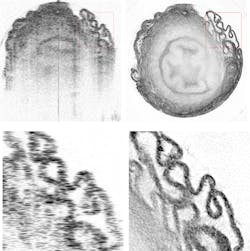

For these proof-of-concept experiments, Zhou took tissue samples such as the bladder or trachea of a mouse, placed them in a tube, and rotated the samples 360° beneath an OCT scanner. The algorithm created a map of each sample’s refractive index, increasing the lateral resolution of the scan by more than 300% while reducing the background noise in the final image. While the study used samples already removed from the body, the researchers believe OCRT can be adapted to work in a living organism.